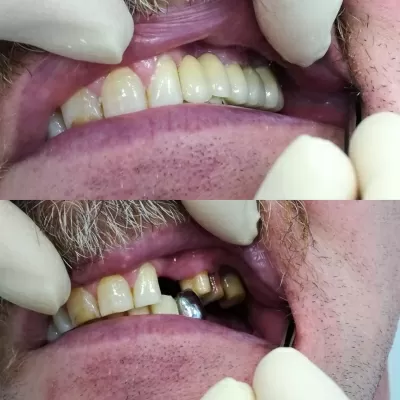

С лета 2018 лечусь в клинике Лигадент у доктора Трошян Тиграна Гамлетовича. За это время доктор восстановил мне все зубы, при лечении которых ранее были допущены, мягко говоря, ошибки. Произвел впечатление очень ответственного, грамотного, образованного специалиста с большим опытом, Это настоящее счастье, когда с тобой работает профессионал такого уровня! Далее мне поставили читать далее